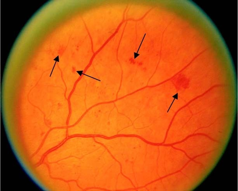

硬性渗出

硬性渗出样例,如箭头所示。其他区域视网膜上更深位置的较暗的黄白色小点是玻璃膜疣,不是硬性渗出。

硬性渗出(HE)是视网膜上的小的白色或黄白色、边界清晰的的沉着物。通常呈现为“蜡状”,闪亮或有光泽。

硬性渗出通常位于视网膜外层,但可能会更偏表面,尤其是在视网膜水肿存在的情况下。硬性渗出可以是独立的小点,也可以是连续的片状斑点,或围绕在视网膜水肿或微血管瘤周围的呈环状病变。在局部视网膜增厚的区域内,融合的硬性渗出可出现在视网膜外层或视网膜下。

注意:硬性渗出(HE)须与玻璃膜疣(一种常见的年龄相关性病理改变)相区分。